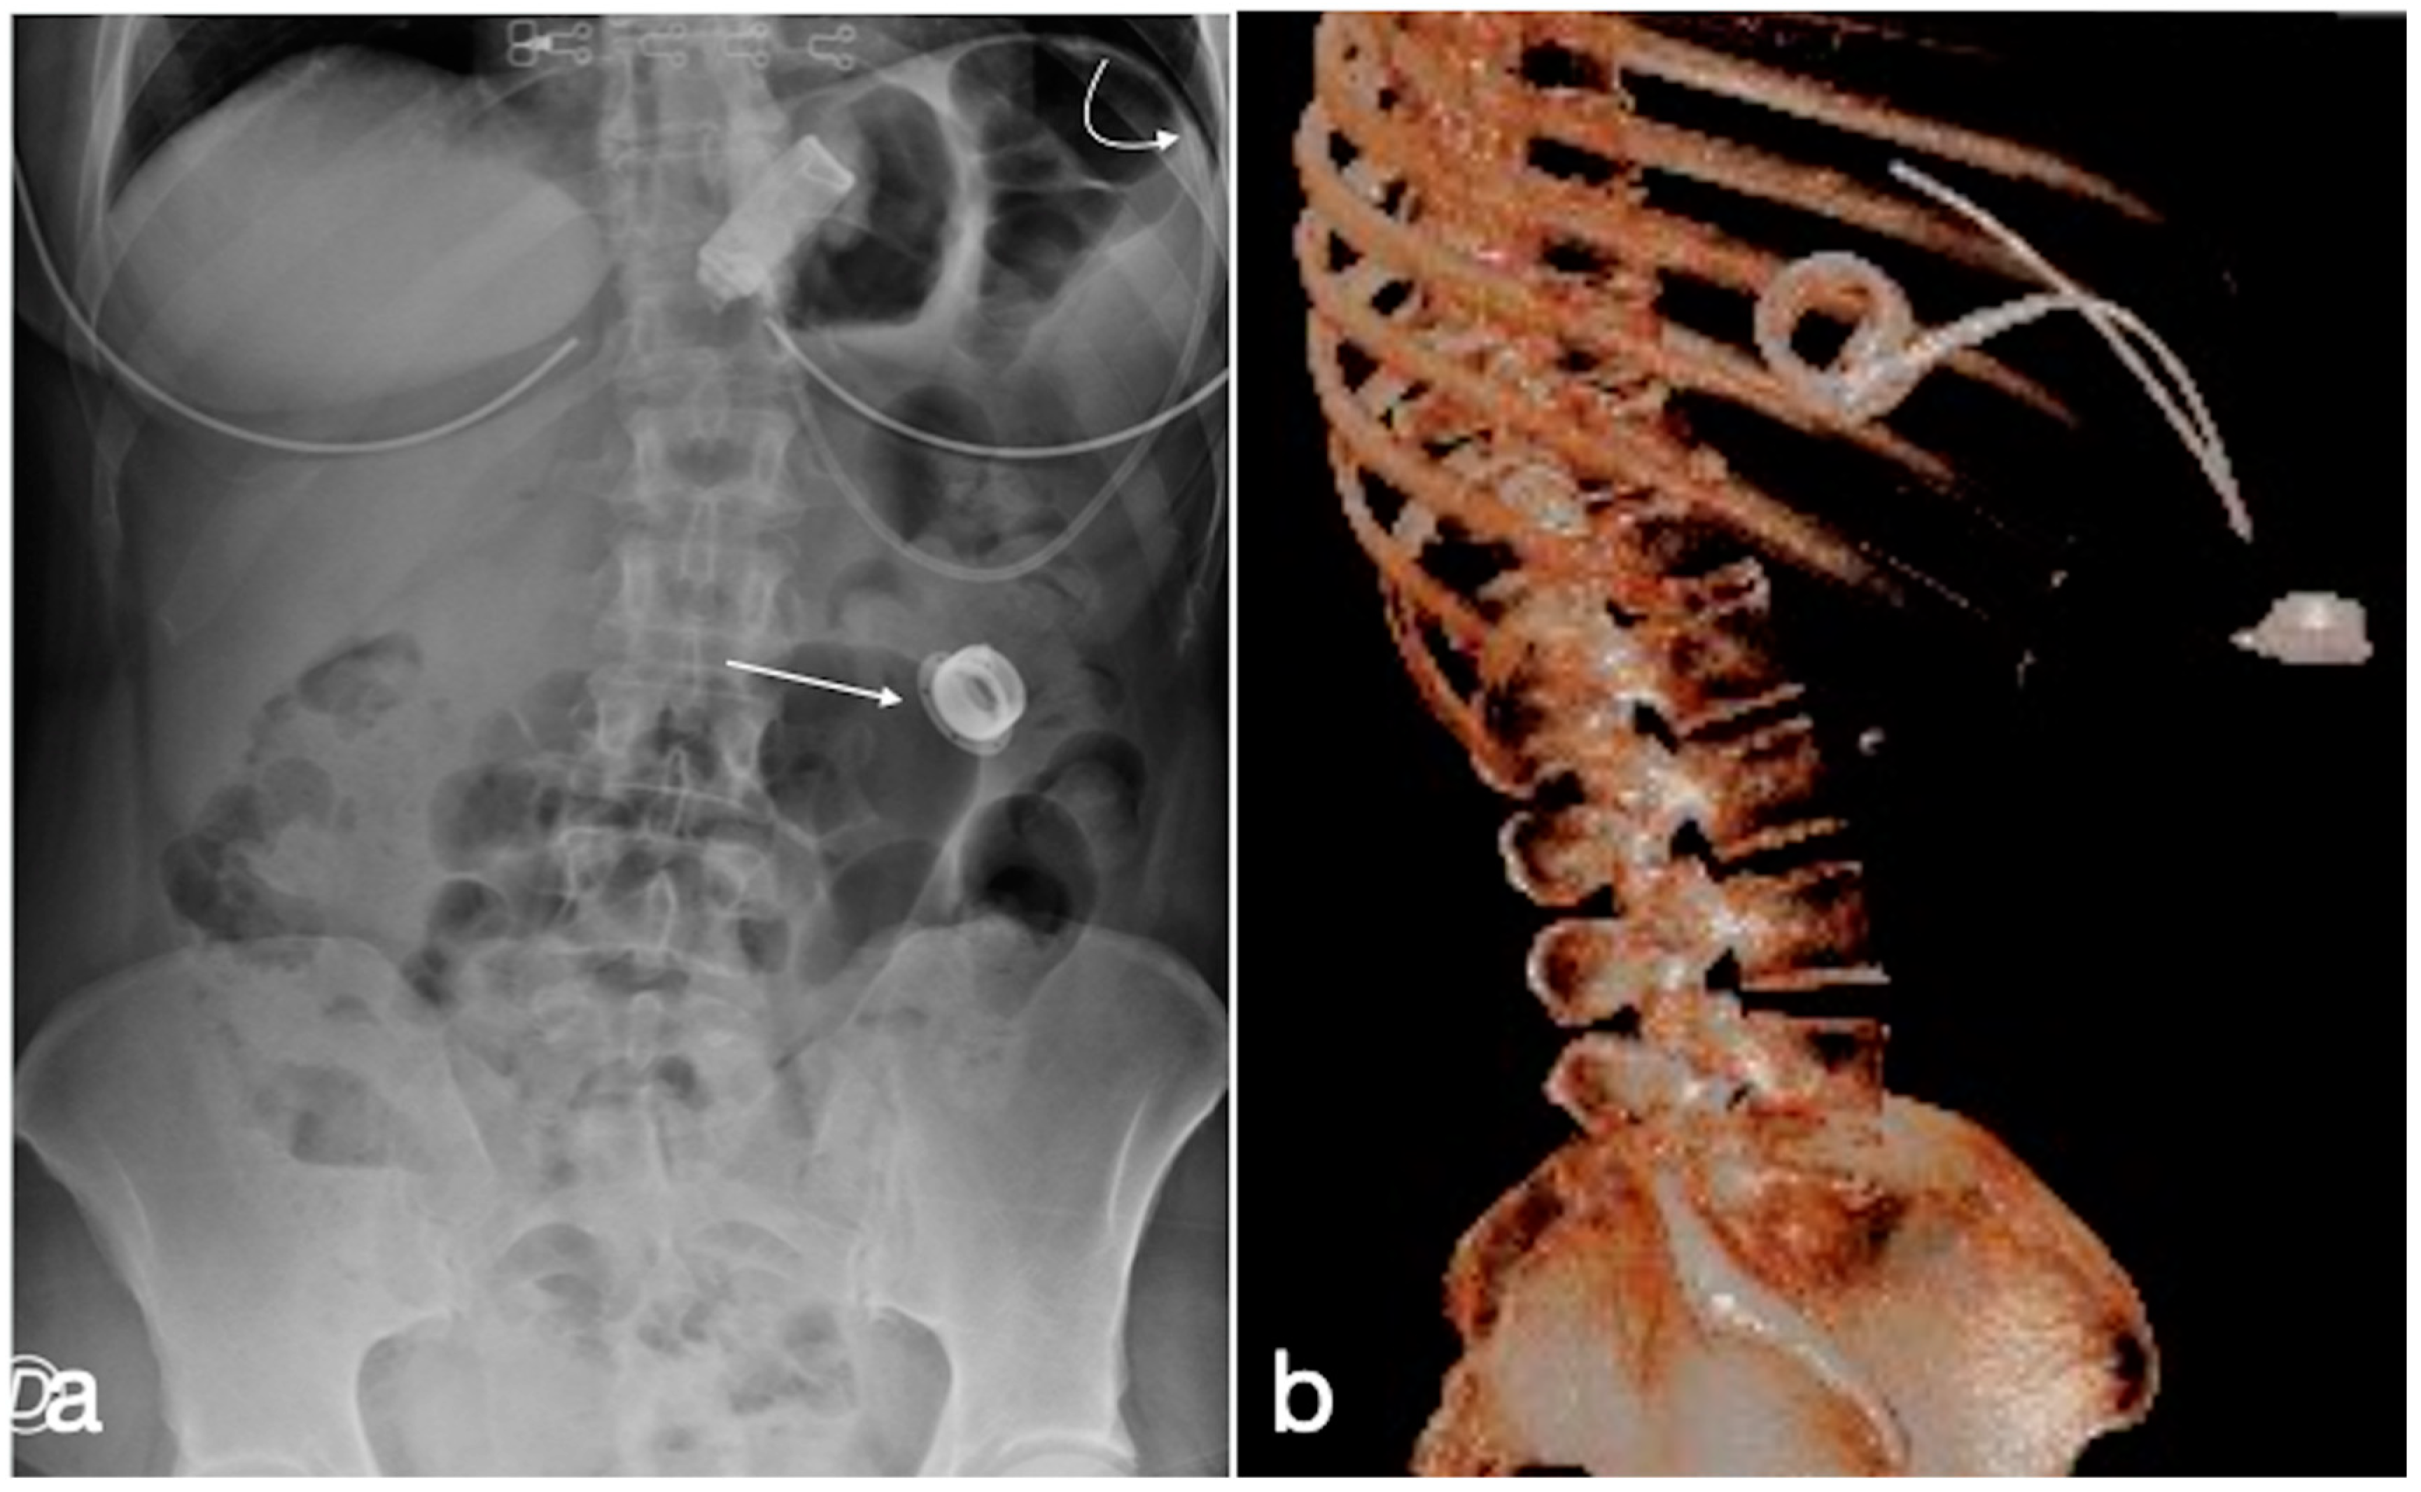

3.4. Unexpected Complication